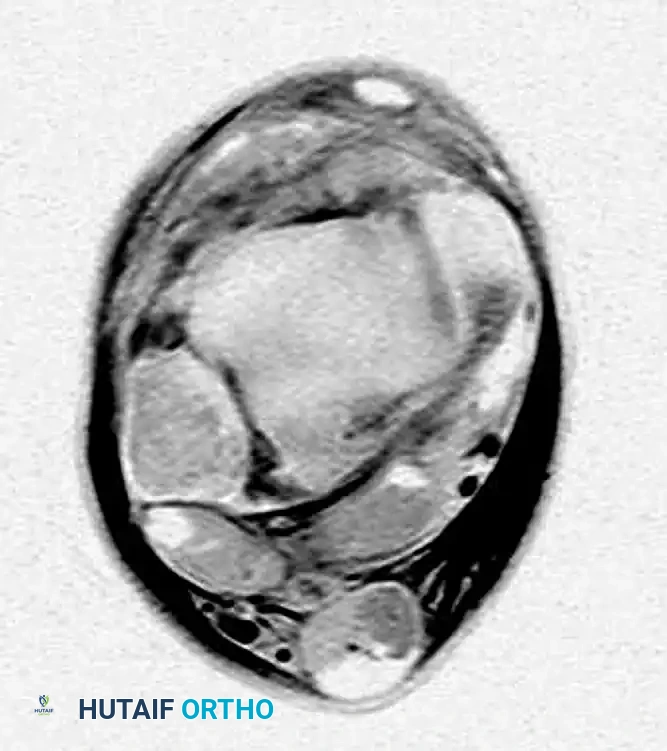

More powerful, high-resolution, three-dimensional MRI studies have revolutionized the diagnostic accuracy of ankle and hindfoot injuries.

- Axial MRI with a local gradient provides optimal visualization of the anterior and posterior talofibular ligaments, the deep layers of the medial collateral (deltoid) ligament, and the tibionavicular ligament.

- Coronal MRI allows a comprehensive assessment of the calcaneofibular, posterior talofibular, tibiocalcaneal, and posterior tibiotalar ligaments.

In both imaging planes, modern MRI allows for the precise differentiation of the deep and superficial layers of the medial collateral ligament, as well as clear demarcation between the syndesmotic complex and the lateral collateral ligaments.

FIGURE 89-6: MRI of a patient with a syndesmosis injury; note the distinct tear of the anterior inferior tibiofibular ligament (AITFL).

Interestingly, Nielson et al. found no direct correlation between tibiofibular clear space and overlap measurements on standard radiographs in patients with MRI-confirmed syndesmotic injuries. However, a medial clear space measurement of more than 4 mm on MRI is highly indicative of deep deltoid ligament incompetence.